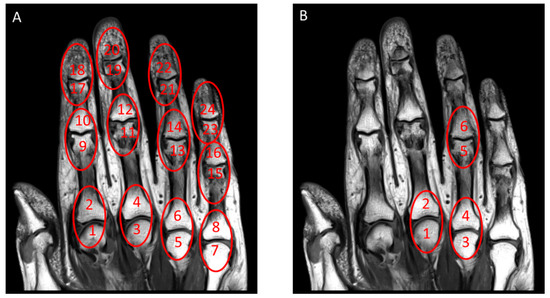

2.4. Development of a Simplified Psoriatic Arthritis MRI Score (sPsAMRIS) and Statistical Analysis

3.1. Simplified Score: sPsAMRIS